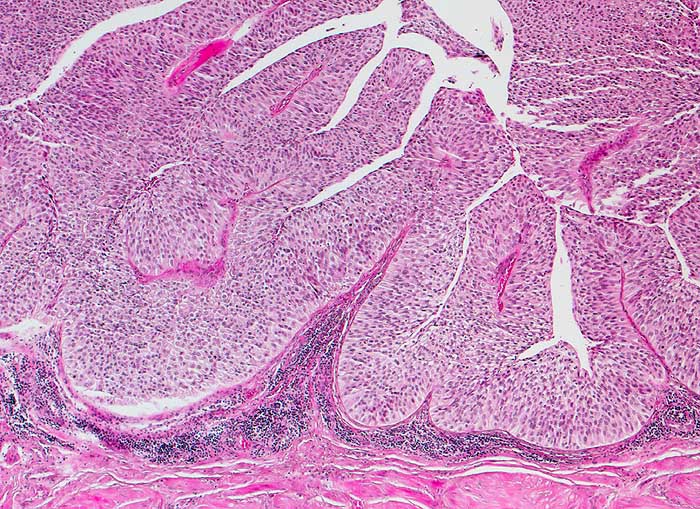

Nicht invasives papilläres Urothelkarzinom, low grade pTa, G2

Das bedeckende Urothel des papillären Tumors ist deutlich verdickt. Verglichen mit normalen Urothel sind die Zellen dieses mässig differenzierten Tumors leicht vergrössert und hyperchromatisch. Dadurch erscheint das Epithel etwas dunkler als normales Urothel. Eine Stromainvasion ist nicht nachweisbar.